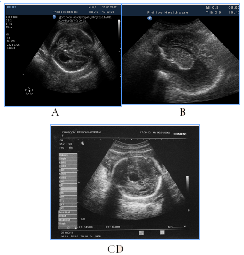

7 cases of callosal agenesis appeared with various echographic variations and associations (Figure 1C) (Figure 1F) (Figure 6) with colpocephaly, interhemispheric cyst, hydrocephalus, absence of the cavum septi pellucidi, as well as with semilobar and lobar HPE and septo-optic dysplasia. From the 7cases of antenatal detection of callosal agenesis, poor GPO were observed in 2cases, poor СPO in 3cases, so postnatal outcome directly depends on the availability of the associated anomalies.

Figure 6Callosal agenesis, different sonographic variants and catamnesis.

Figure 6 Callosal agenesis, different sonographic variants and catamnesis. A) Associated callosal agenesis combined with colpocephaly ("tear-drop" configuration of the posterior horns of the lateral ventricles), progressive moderate hydrocephalus, without neonatal complications, long-term severe neurological disorders and neuro-psychological retardation. B) Moderate hydrocephalus, partial agenesis of the corpus callosum and subependymal cyst, infant death in 5months. C) Syndromal callosal agenesis, sonographic variant with absence of the cavum septi pellucidi and ventriculomegaly, neonatal death. D) Isolated callosal agenesis with an expanded and elevated third ventricle in the form of the "inter-hemispheric cyst», no neonatal and infant complications.